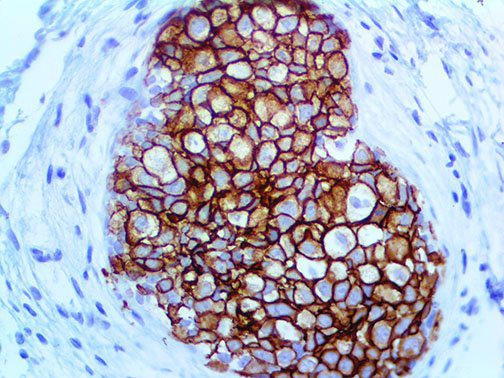

It is the ICU physician who is most likely to witness one of the deadliest manifestations of the abnormal immunological response, the cytokine storm syndrome (CSS). This response is also referred to by some as the cytokine release syndrome (CRS). CSS is characterized by continuous activation and expansion of macrophage and lymphocyte populations, which secrete large amounts of cytokines, causing the cytokine storm. This massive cytokine release is akin to hemophagocytic lymphohistiocytosis (HLH) disease, a syndrome characterized by initial unchecked and persistent activation of cytotoxic T lymphocytes and NK cells.

Clinical and laboratory manifestations of HLH include fever, enlarged liver and/or spleen, neurologic dysfunction, coagulopathy, liver dysfunction, cytopenias (i.e., low levels of erythrocytes, leukocytes, and/or platelets), hypertriglyceridemia, hyperferritinemia, hemophagocytosis, and eventually diminished NK cell activity as the immune system becomes progressively paralyzed. HLH can be familial (primary HLH) or secondary to another disease process (sHLH), such as rheumatic disease, in which it is referred to as macrophage activation syndrome (MAS, characterized by elevated ferritin).